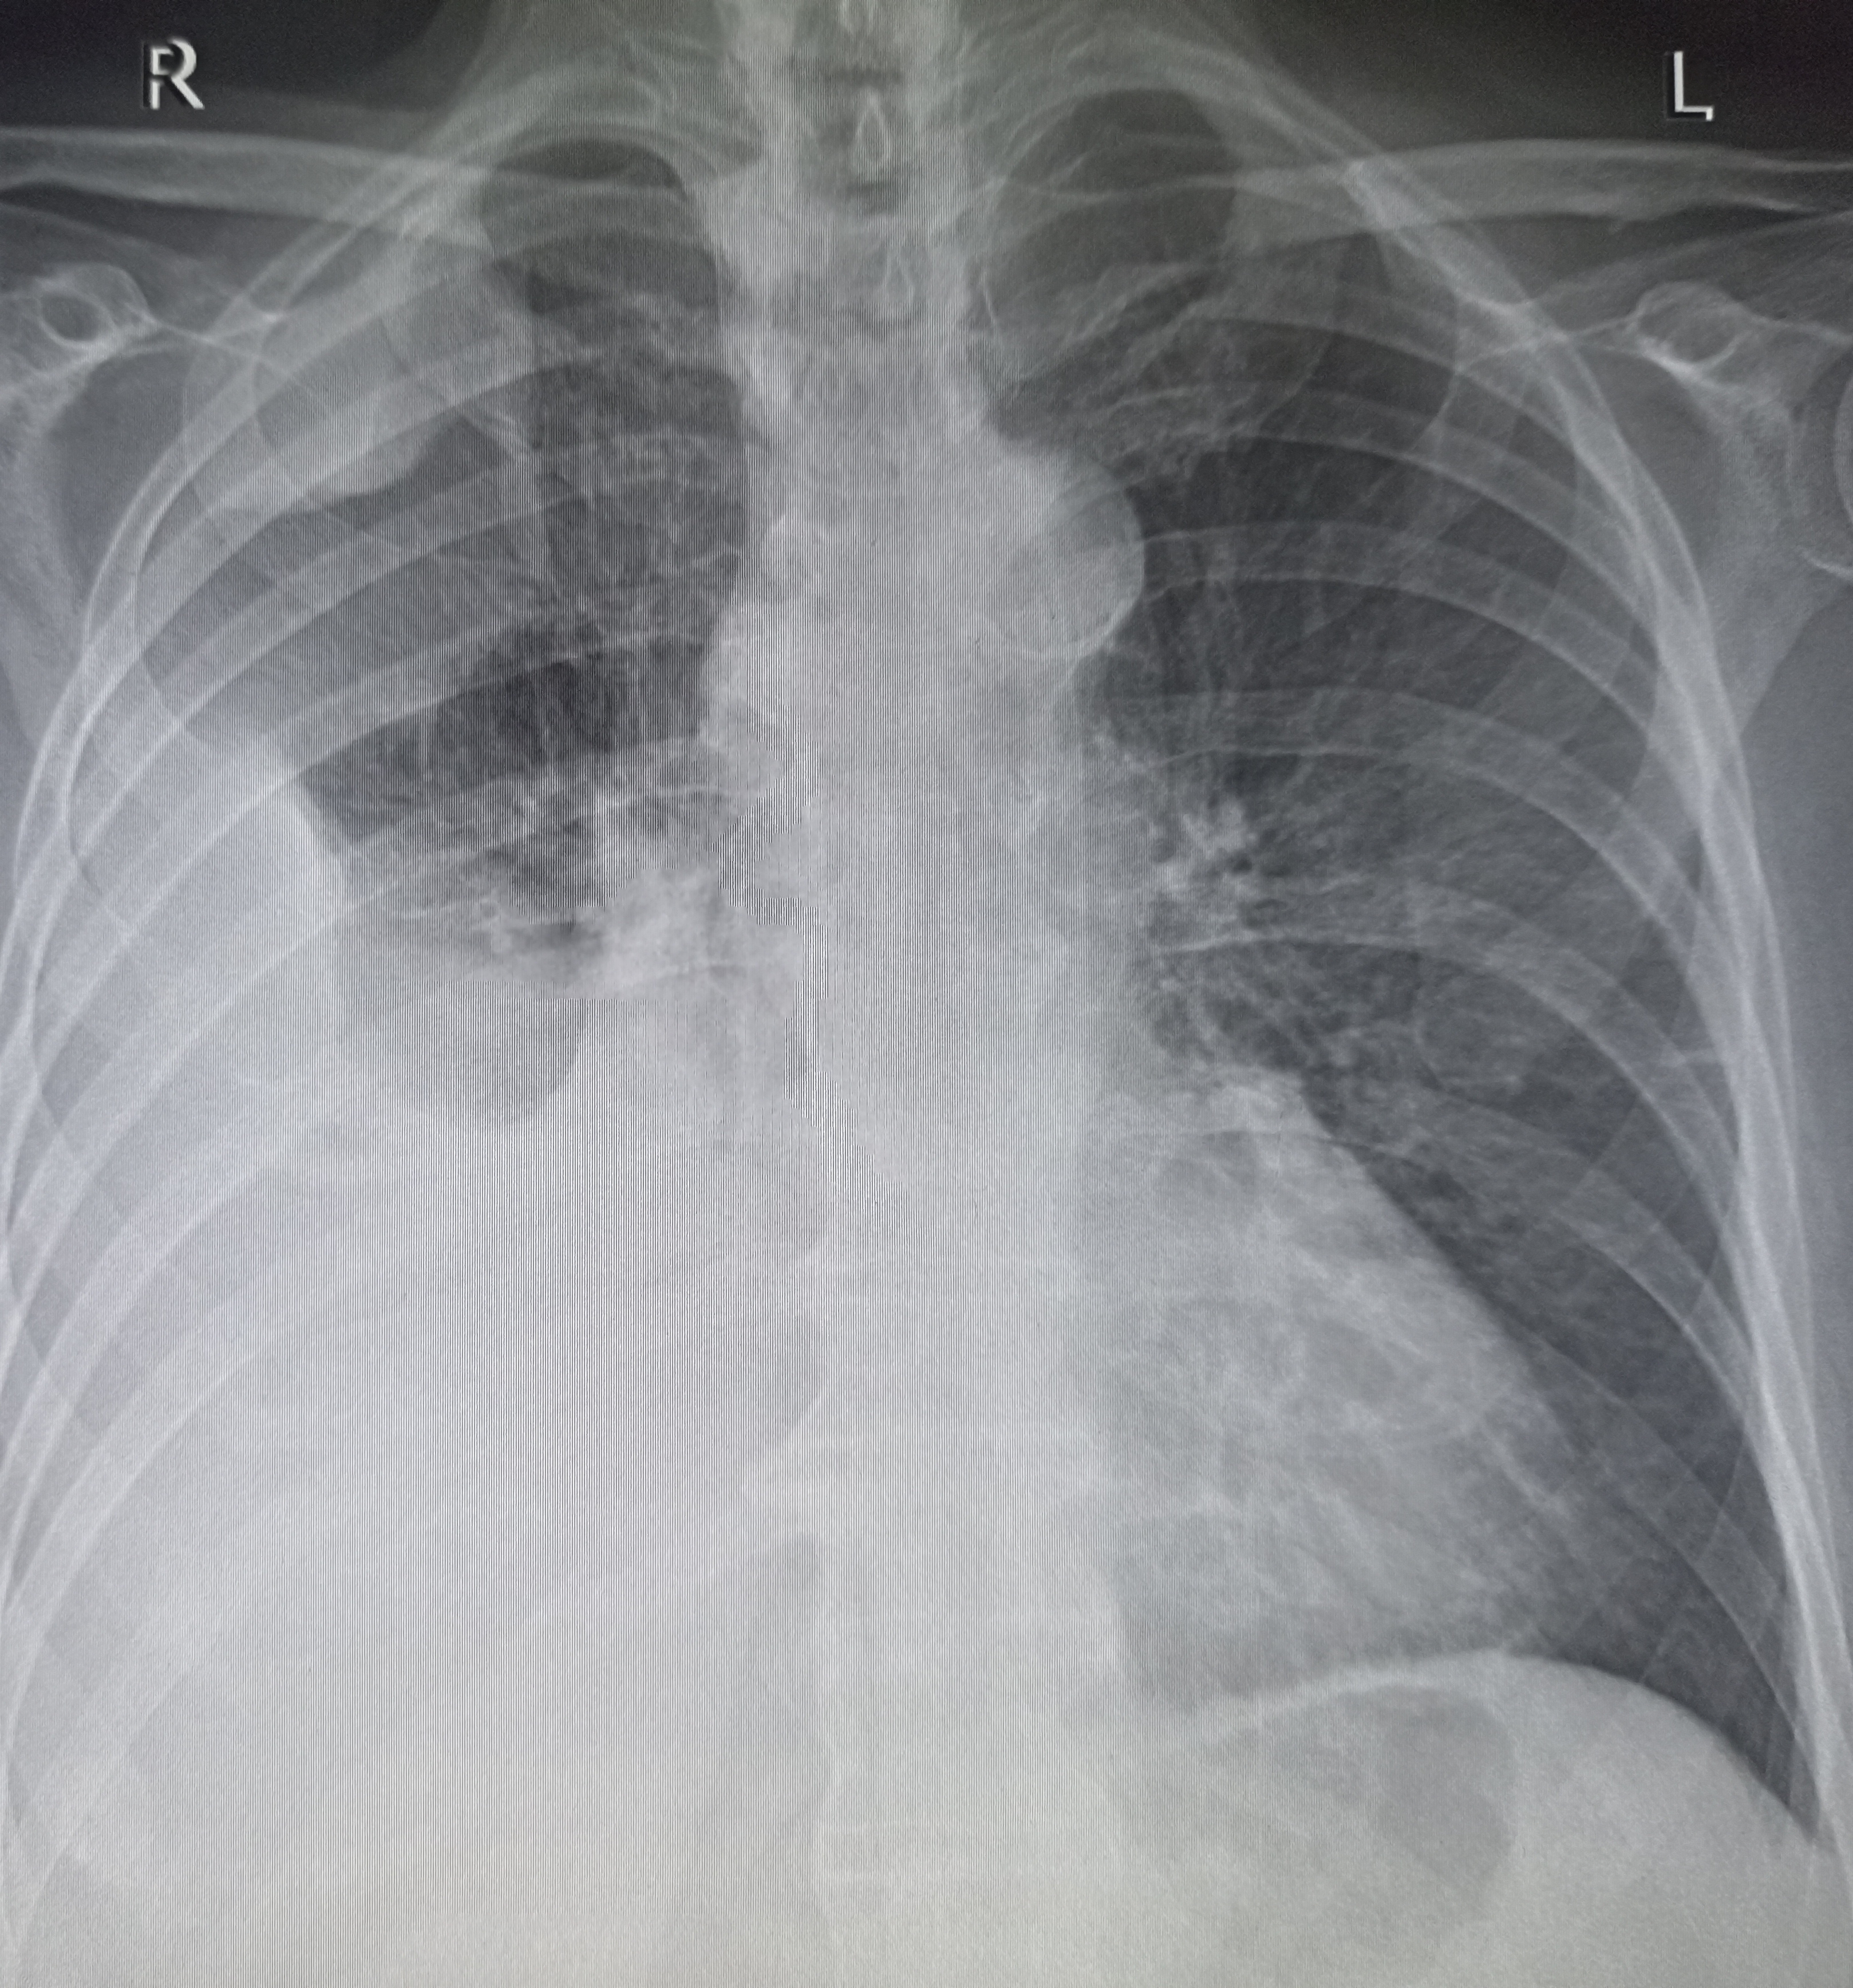

IMG20251016100939.jpg

Найдите поломку!

Где пиздецома?

Аноним 16/10/25 Чтв 08:56:19 #12 №325599559

IMG20251008114159.jpg

Чо тут у нас?

>>325599559

Типичный рак легких

Аноним 16/10/25 Чтв 08:58:28 #14 №325599625

>>325599617

Сфигаль?

>>325599636

Батя умер от такого, мне лень искать снимки

Аноним 16/10/25 Чтв 09:17:43 #25 №325600106

>>325600080

пизда твоей матушки

Аноним 16/10/25 Чтв 09:18:08 #26 №325600117

>>325599918

Оператор лаборант же, он фоткает я описываю.

Аноним 16/10/25 Чтв 09:20:05 #27 №325600162